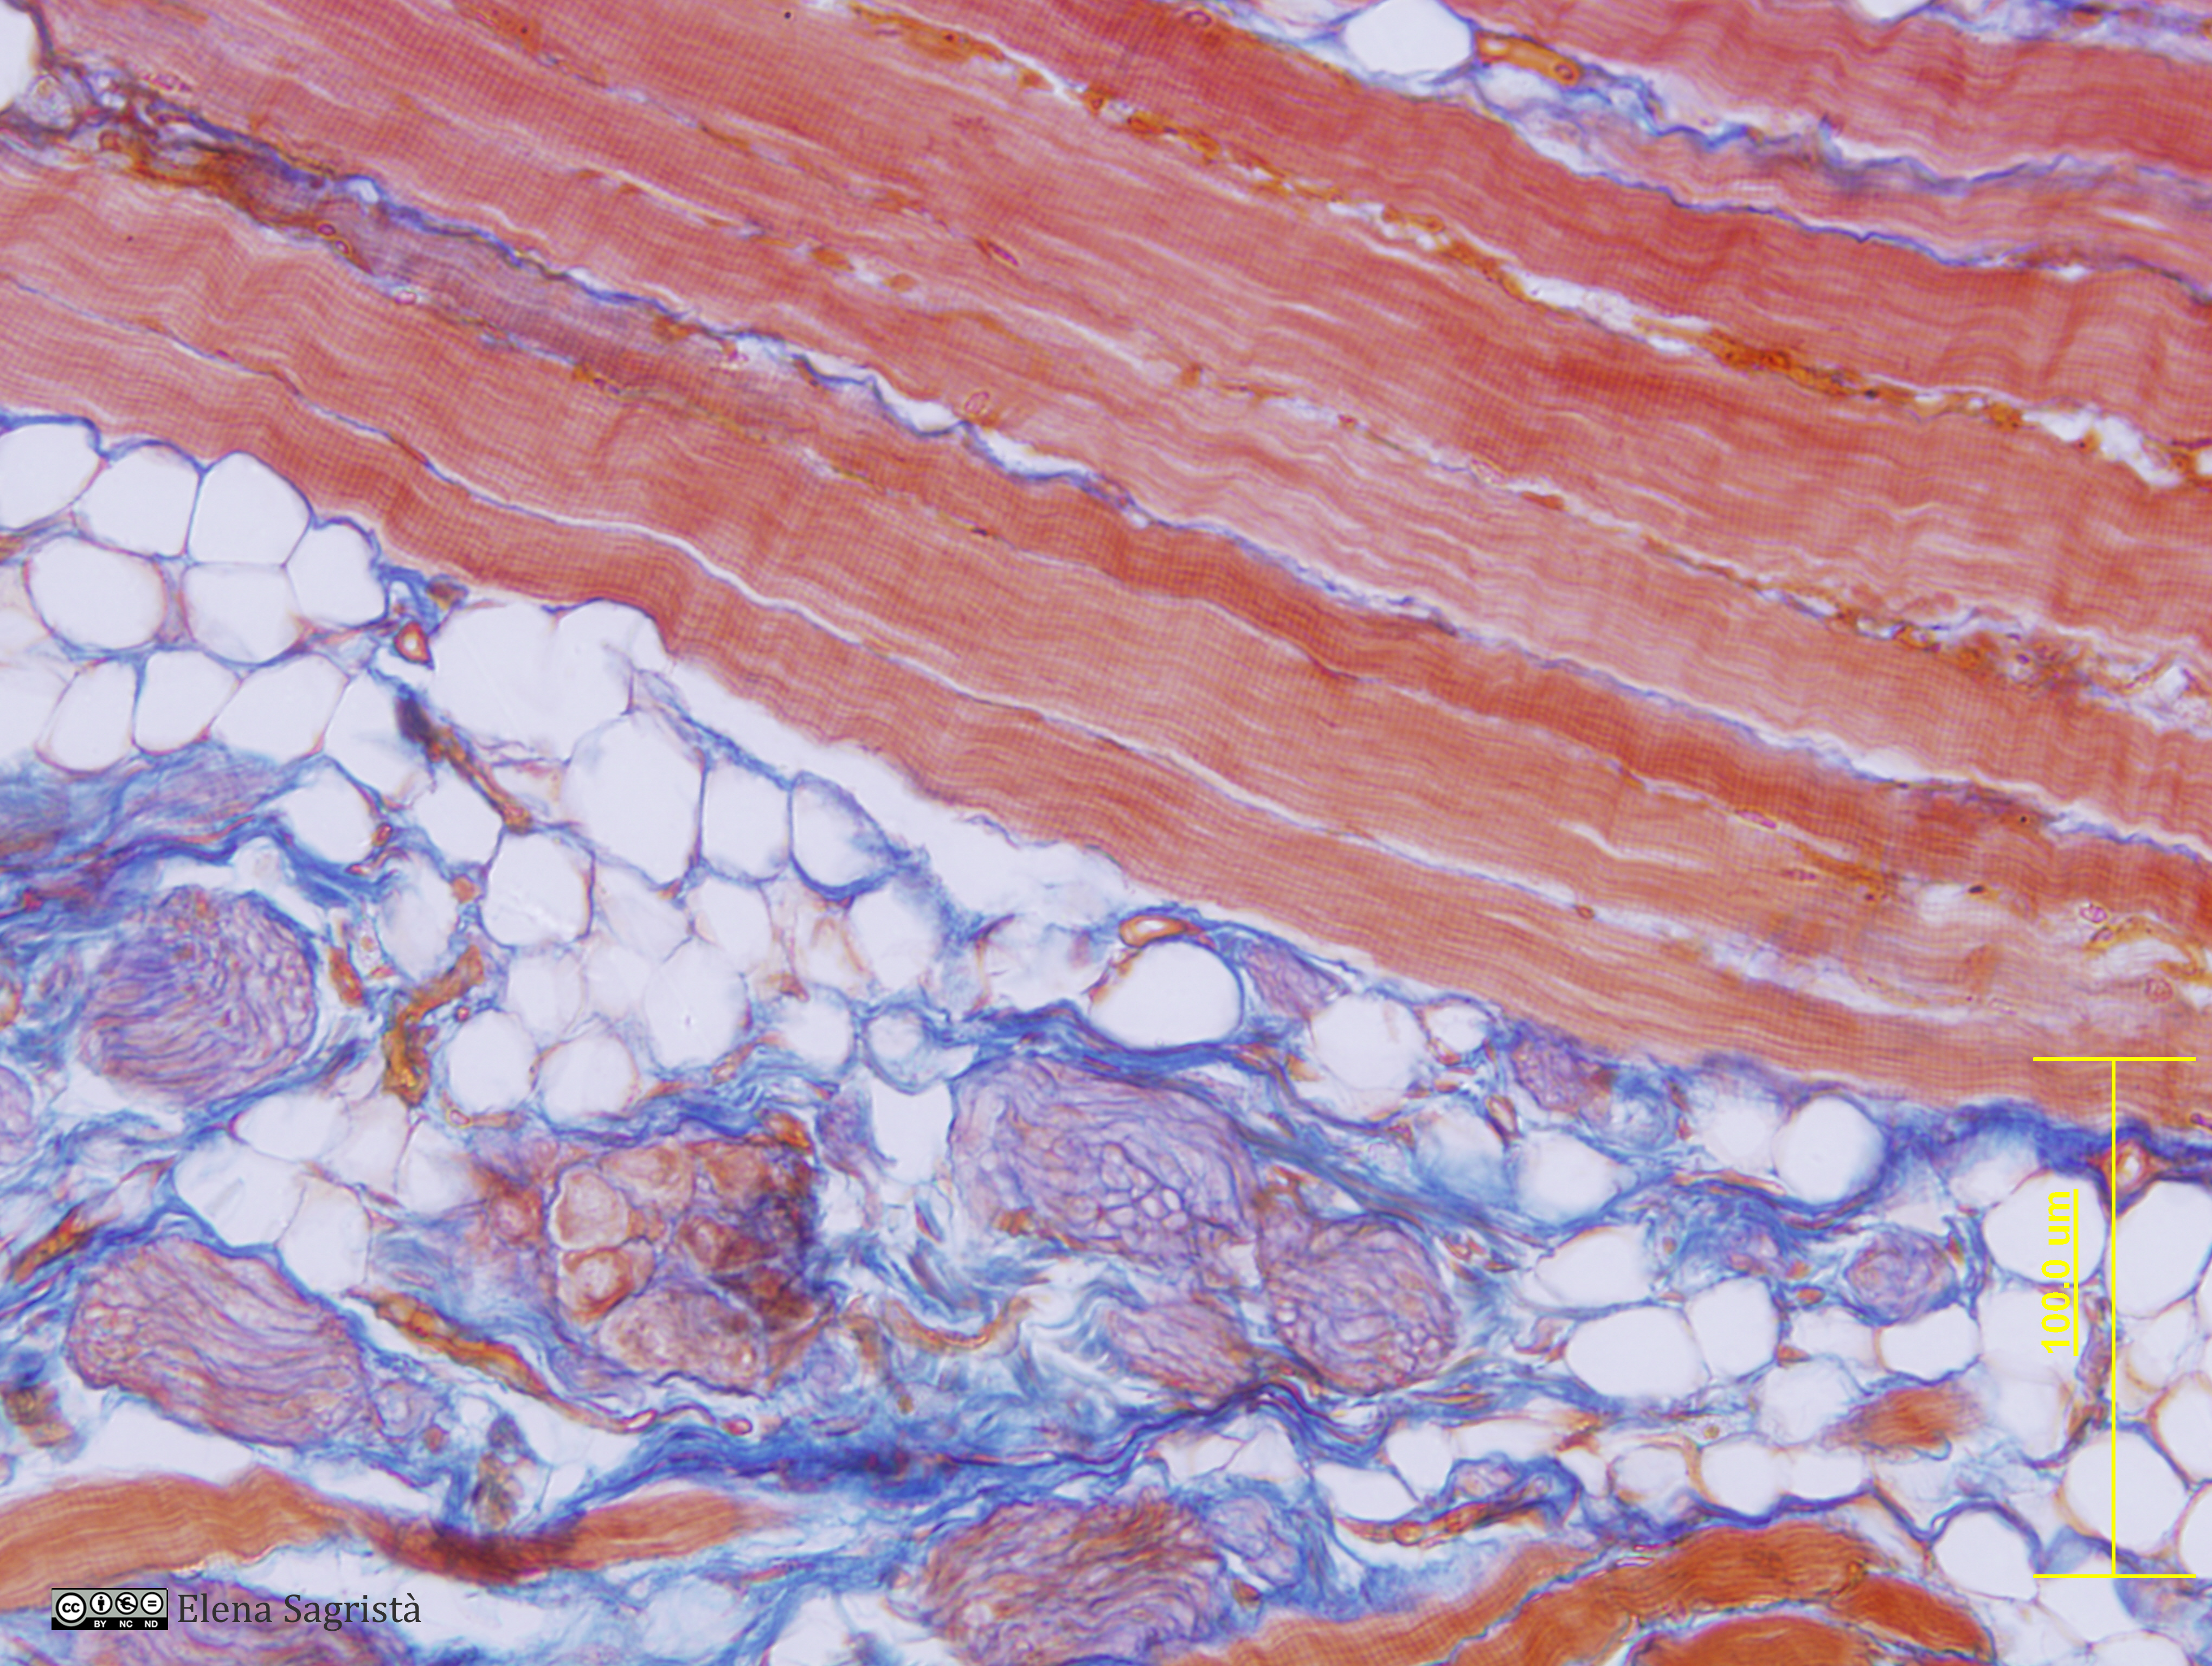

Histologia imatges: 07 Teixit muscular

Imatges de preparacions histològiques de Teixit muscular. Microscopia òptica.